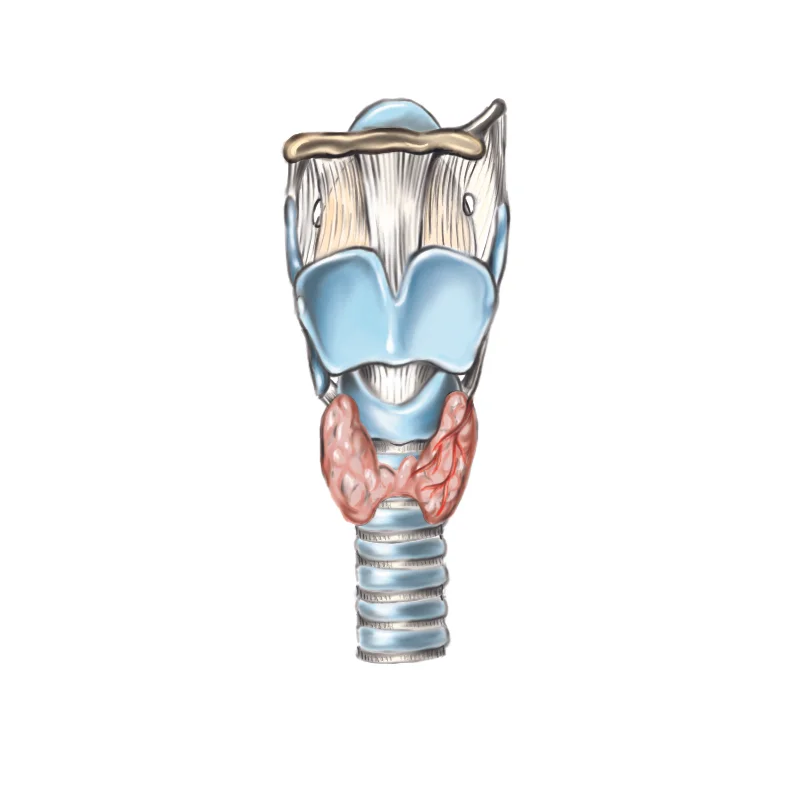

Biomedical art is a form of biological illustration that helps record and disseminate medical, anatomical, and related knowledge. It translates complex technical medical information into visual artwork to support research, patient care and education, public relations, and marketing objectives.